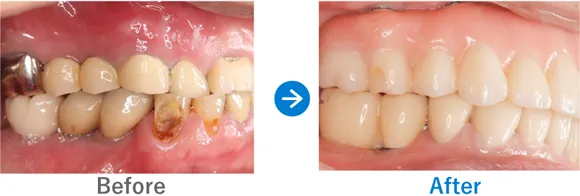

ブリッジで両隣の歯もダメに…。インプラント治療後は奥歯でしっかり噛めるように!

右下7はかなり前に抜歯後、ブリッジ治療済み。左下6は抜歯後、義歯を入れたがほとんど使っていない

インプラント4本:右下6・7、左下6・7

1,249,500円(内訳:GBR、インプラント4本(ネオデント)、ガイド、仮歯、セデーション、骨補填材、保証20年)

治療結果

来院時の検査で、骨はやせてはいたものの治っている状態だったので、インプラント埋入と同時に骨補填をし、下顎の左右に2本ずつインプラントを埋入し治療完了しました。しっかり噛めるようになり患者様も喜んでおられます。今後はナイトガードを使用して、ブラキシズム(無意識下の歯ぎしり、食いしばりなど)の予防をしていく予定です。